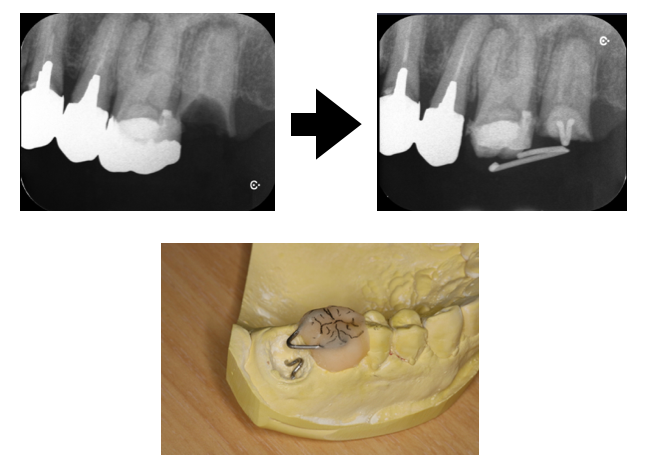

他院で抜歯と言われた症例①